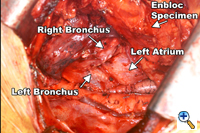

Figure 2. The en-bloc specimen is completely mobilized, revealing the left lung, the tracheal bifurcation and the pericardium. |

Division of both pulmonary ligaments (left and right) completes the esophageal mobilization (Figure 2). For tumors traversing the hiatus, a one-inch cuff of diaphragm is circumferentially excised en-bloc with the specimen using electrocautery. The completed dissection clears all nodal tissue in the middle and lower mediastinum including the right and left paraesophageal, parahiatal, para-aortic, subcarinal, bilateral hilar, and aortopulmonary lymph nodes.